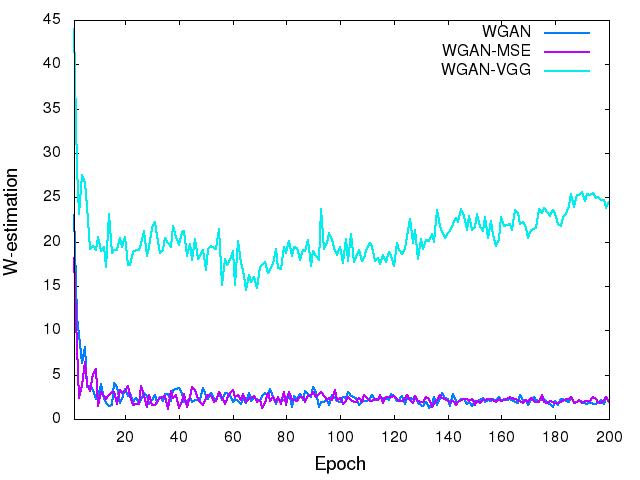

To visualize the convergence of the networks, we calculated the MSE loss and VGG loss over the 5,056 image patches for validation according to Eqs. (4) and (6) after each epoch. Fig. 4 shows the averaged MSE and VGG losses respectively versus the number of epochs for the five networks. Even though these two loss functions were not used at the same time for a given network, we still want to see how their values change during the training. In the two figures, both the MSE and VGG losses decreased initially, which indicates that the two metrics are positively correlated. However, the loss values of the networks in terms of MSE are increasing in the following order, CNN-MSEWGAN-MSEWGAN-VGGCNN-VGG (Fig. 4a), yet the VGG loss are in the opposite order (Fig. 4b). The MSE and VGG losses of GAN network are oscillating in the converging process. WGAN-VGG and CNN-VGG have very close VGG loss values, while their MSE losses are quite different. On the other hand, WGAN perturbed the convergence as measured by MSE but smoothly converged in terms of VGG loss. These observations suggest that the two metrics have different focuses when being used by the networks. The difference between MSE and VGG losses will be further revealed in the output images of the generators.

In order to show the convergence of WGAN part, we plotted the estimated Wasserstein values defined as in Eq. (3). It can be observed in Fig. 4(c) that increasing the number of epochs did reduce the W-distance, although the decay rate becomes smaller. For the WGAN-VGG curve, the introduction of VGG loss has helped to improve the perception/visibility at a cost of a compromised loss measure. For the WGAN and WGAN-MSE curves, we would like to note that what we computed is a surrogate for the W-distance which has not been normalized by the total number of pixels, and if we had done such a normalization the curves would have gone down closely to zero after 100 epochs.